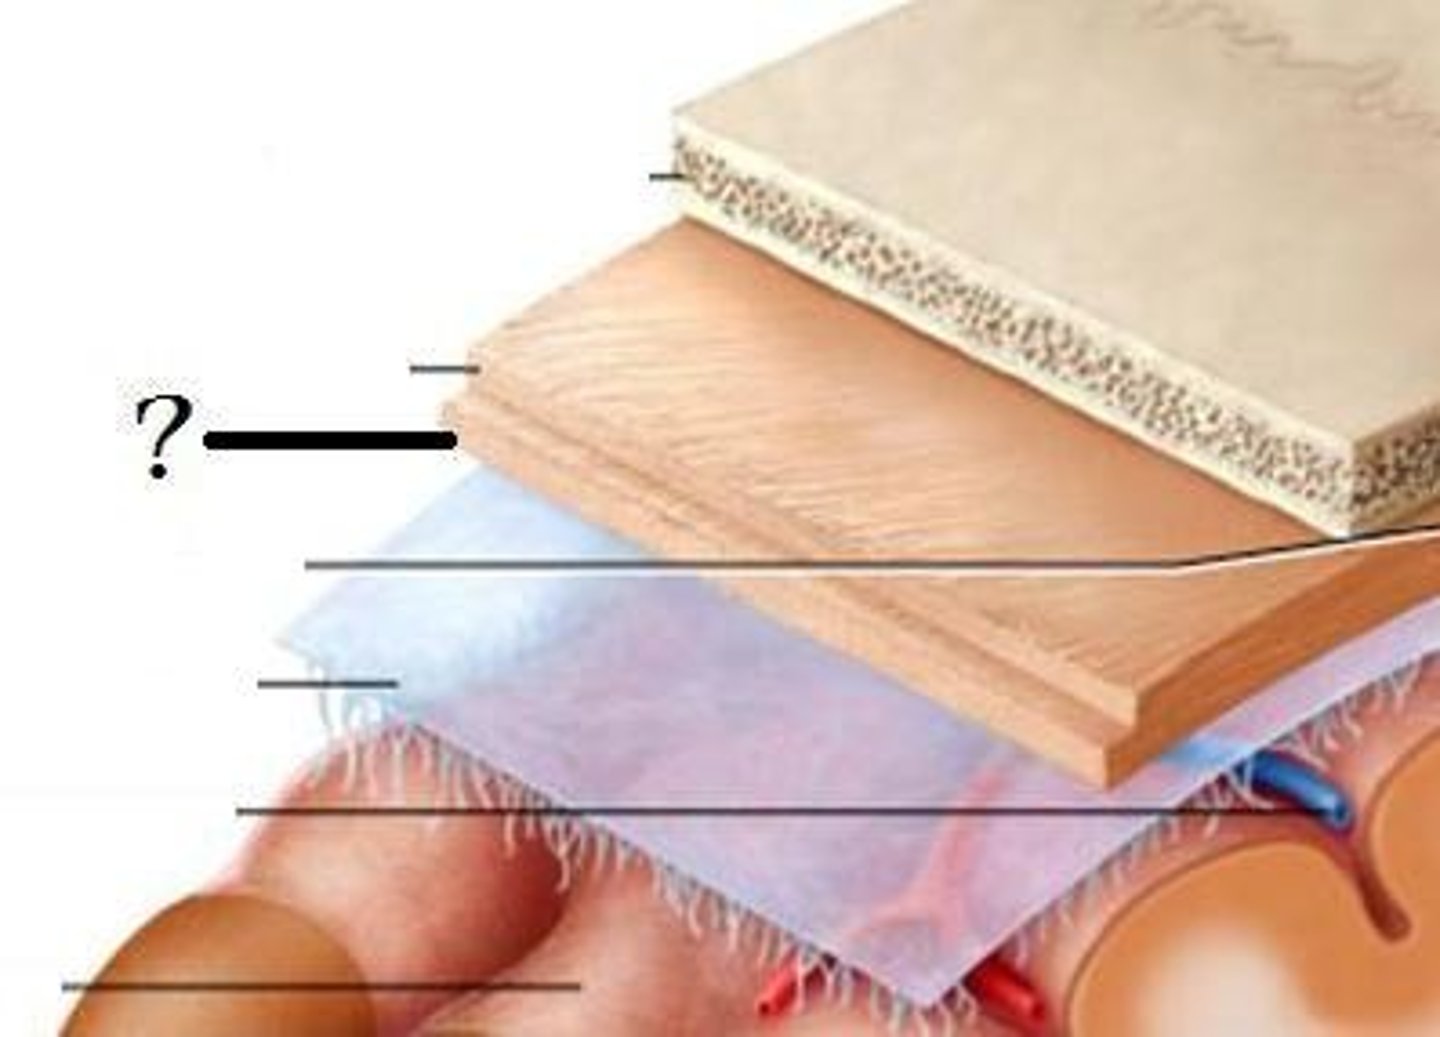

Meninges

-Three connective tissue membranes that envelope the CNS

-Protect the CNS and provide structural framework for its arteries and veins

Meninges Location

-Lies between the nervous tissue and bone

Cranial dura mater

-Outer periosteal

-Inner meningeal

-Folds inward to extend between parts of the brain

Cranial dura mater location

-Layers separated by dural sinuses

-Pressed closely against cranial bones

=No epidural space

=Only attached to bone around foramen magnum, stella turcica, crista galli, and sutures of the skull

Periosteal

-Equivalent to periosteum of cranial bones

Meningeal

-Continuous into vertebral canal and forms dural sheath around spinal cord

Dural sinuses

-Separates layers of cranial dura mater

Arachnoid mater

-Transparent membrane over brain surface

Subarachnoid space

-Separates arachnoid mater from pia mater below

Subdural space

-Separates arachnoid from dura mater above in some spaces

Pia mater

-Very thin membrane that follows contours of brain, even dipping into sulci

-Not usually visible without a microscope